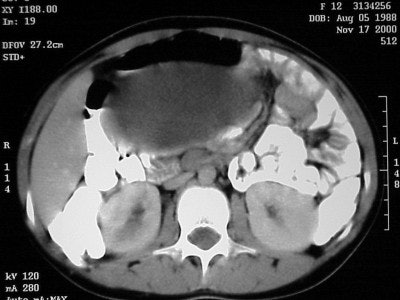

Axial images (Figures CT 10 and CT 11) show a mass beginning just below the kidneys on the left side and extending almost through the pelvis. The child was diagnosed with Wilm’s tumor of the left kidney.

![]() |

| Figure CT 10 |

She underwent a left nephrectomy and chemotherapy and recovered well.